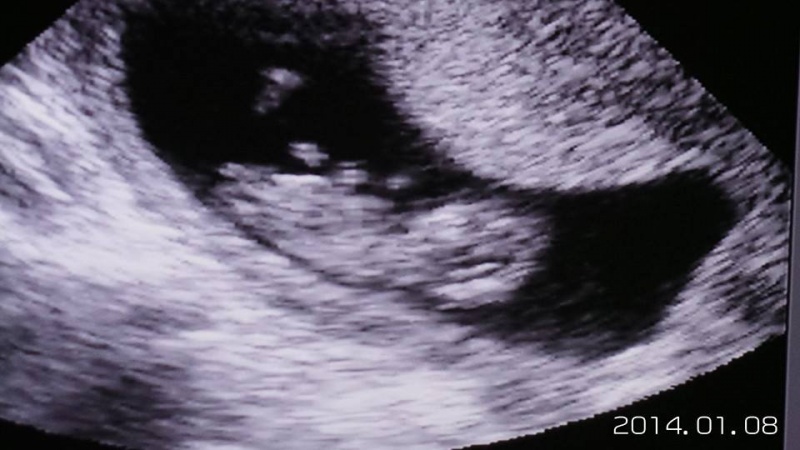

csinált egy hüvelyi uhut. közölte hogy látja a babaát most mit akarok. Én meg néztem rá nem értvén mire gondol. erre közli hogy szülni akarok vagy elvetettem?  mikor közöltem hogy természetesen szülök. adott egy fotót meg beutalókat a laborba. A baba 9 mm és dobog a szíve. 3 hét múlva kontrol uhu.

Kép